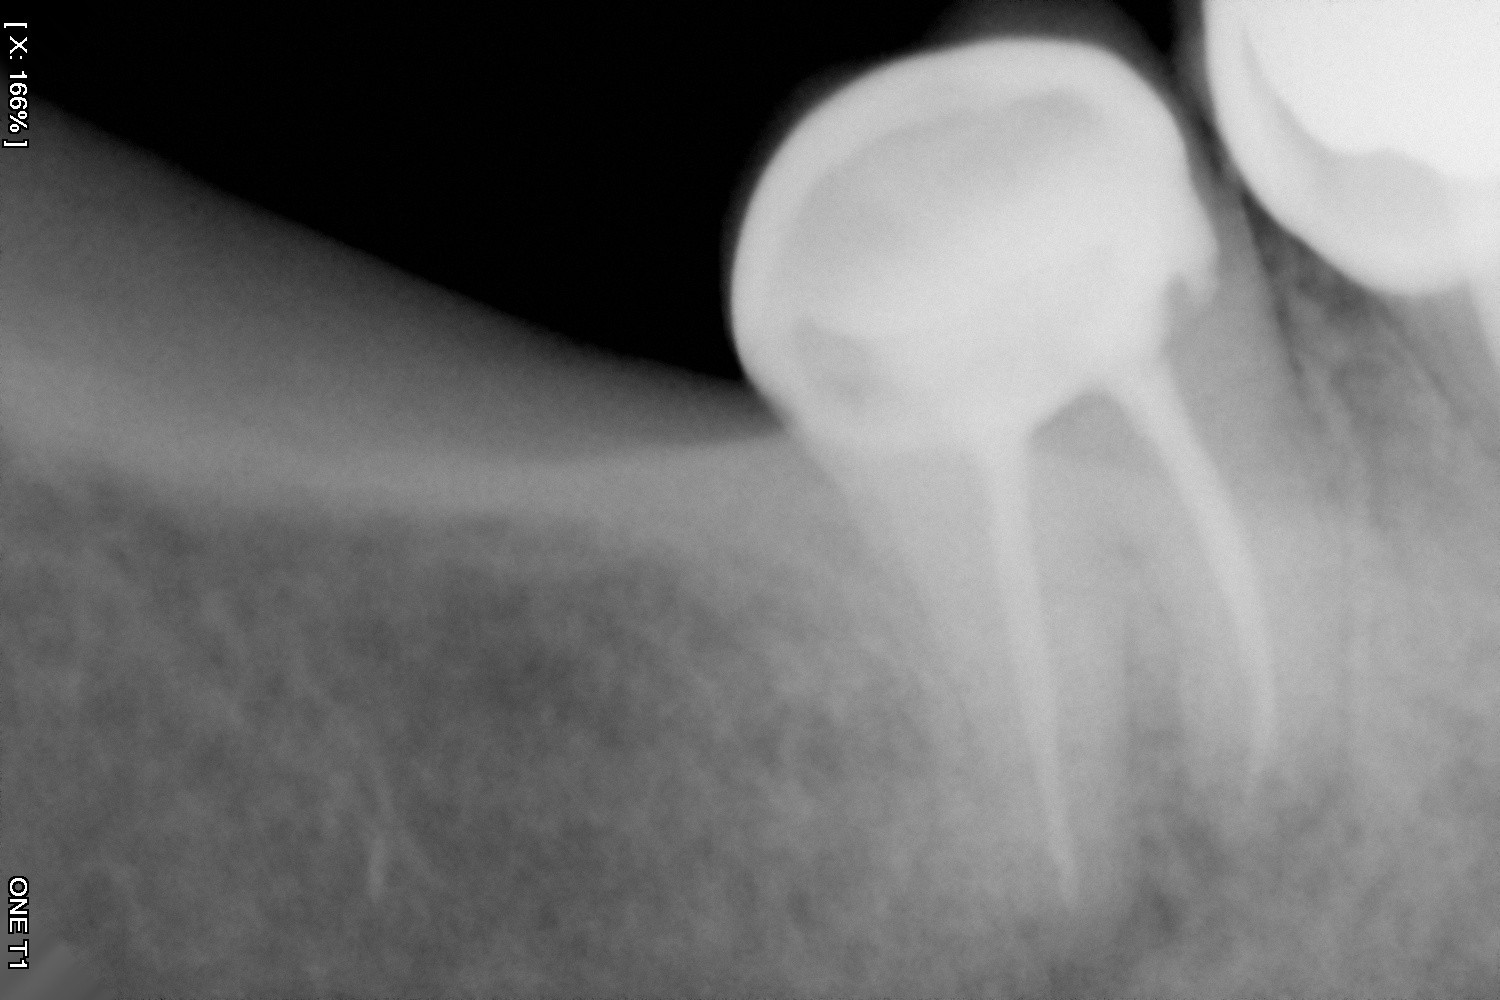

Es la especialidad que se encarga de retirar el nervio del diente cuando éste ha sido afectado por una caries, por un golpe o simplemente por requerimiento de un procedimiento de rehabilitación que esté causando sintomatología.

Y en DentPro realizamos tratamientos endodónticos con la más avanzada tecnología, utilizando sistemas rotatorios y radiografías digitales.